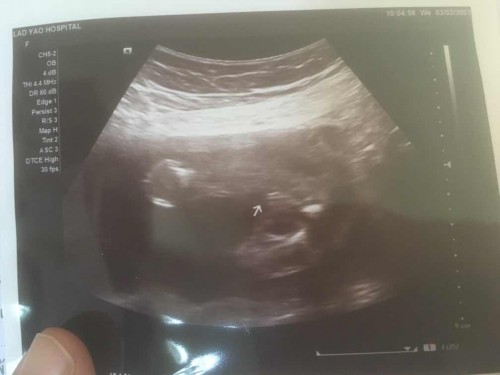

ช่วยดูหน่อยค่ะ ผู้หญิง รึ ผู้ชาย ค่ะ กำหนดคลอด18ก.ค 2564

น่าจะหญิงนะคะ หมอบอกว่าเพศอะไรคะ